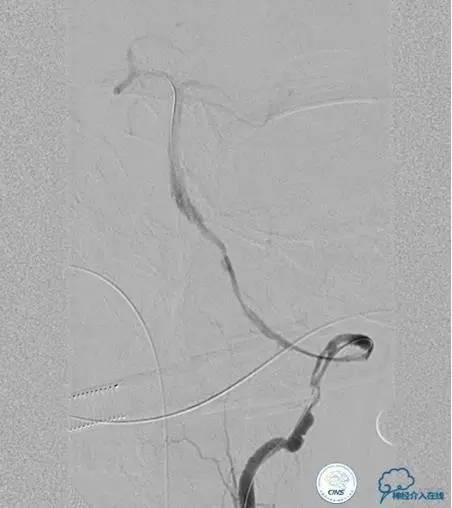

▼开通

出院情况:头晕症状消失,构音障碍缓解,进食无呛咳,饮水实验(-),右侧肢体远端肌力恢复到Ⅰ级。